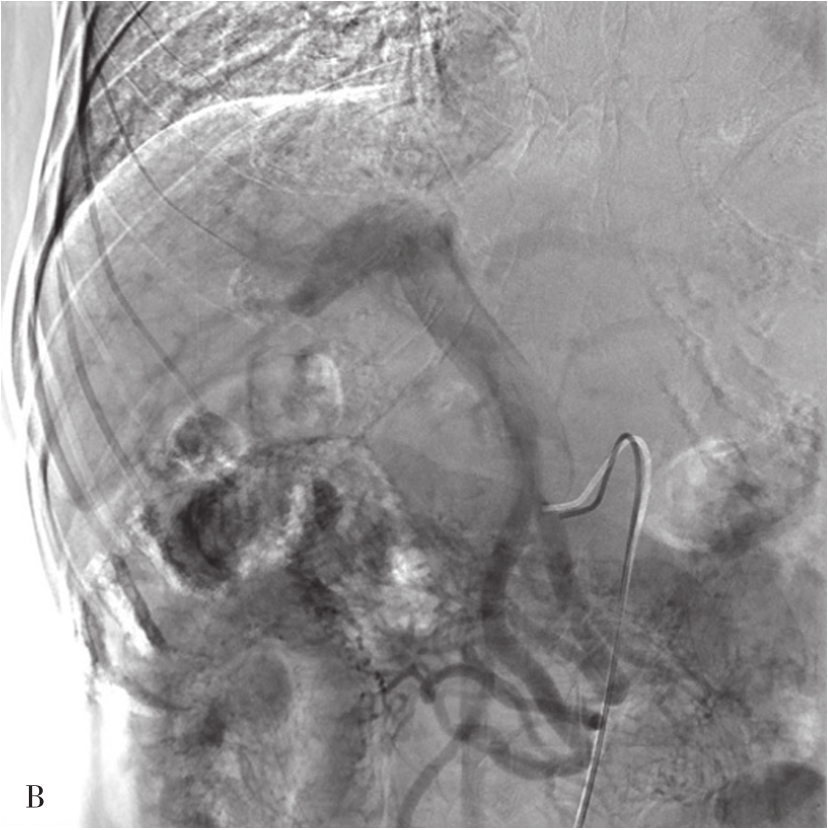

采用Seldinger技术穿刺股动脉成功后,插管入肝总动脉,行动脉造影,常规采用非离子碘对比剂,以6~8mL/s,总量20~30mL的速率注入,并连续摄片12秒以上,以观察肝总动脉及其分支,动脉供养器官的实质期和静脉回流的情况(图5-21-49)。如需要进一步观察肝脏的情况,可以超选择插管进入肝固有动脉或者肝左、右动脉。如经股动脉插管不成功,亦可选择经肱动脉和桡动脉等上入路。显示肝动脉和肝实质及回流静脉的情况,可有:①常规X线摄片检查,已被数字减影血管造影(digital subtraction angiography,DSA)取代;② DSA,是应用计算机辅助成像。动脉插管成功后,注入造影剂之前,首先进行第一次成像,并用计算机将图像转换成数字信号储存起来。注入造影剂后,再次成像并转换成数字信号。两次数字相减,消除相同的信号,得知一个只有造影剂的血管图像。这种图像可以更清晰和直观显示血管结构。显示血管的情况,除插管进入动脉后注入对比剂外,亦可经静脉注入对比剂后,根据对比剂的循环时间观察其显示的相应的血管。如CT动脉造影(CT angiography,CTA),将CT增强技术与薄层、大范围、快速扫描技术相结合,通过合理的后处理,清晰显示全身各部位血管细节,具有无创和操作简便的特点,对于血管变异、血管疾病以及显示病变和血管关系有重要价值。

图5-21-49 经股动脉穿刺行肝总动脉造影

A.可观察肝总动脉及其分支,动脉期可见肝右下富血供性占位病变(白色箭头);B.静脉期可见脾静脉和门脉干及其分支显示

本节主要介绍的是临床上常用的DSA。其适应证主要是:①观察肝脏动脉和门静脉等血管的病变和解剖变异,如血管畸形、动静脉瘘、血管狭窄或动脉瘤。②为肝脏占位性病变的位置和性质的诊断提供影像学证据(图5-21-50)。对富血供的病变,有可能发现直径小于5mm的病灶。③为经肝动脉的治疗建立了途径。如肝肿瘤的化疗栓塞、出血动脉的栓塞等。其禁忌证是相对的,主要是出凝血功能严重障碍和肾功能衰竭。肝动脉造影虽然是有创的检查,但其严重并发症的发生率低于1%。主要与动脉穿刺插管、对比剂的应用等相关。

图5-21-50 肝动脉造影

显示肝癌并门脉右支及主干癌栓,动脉期可见供养静脉癌栓的数条并行细小动脉(条纹征),为癌栓的供养动脉。RHA:肝右动脉;GDA:胃十二指肠动脉;SA:脾动脉。